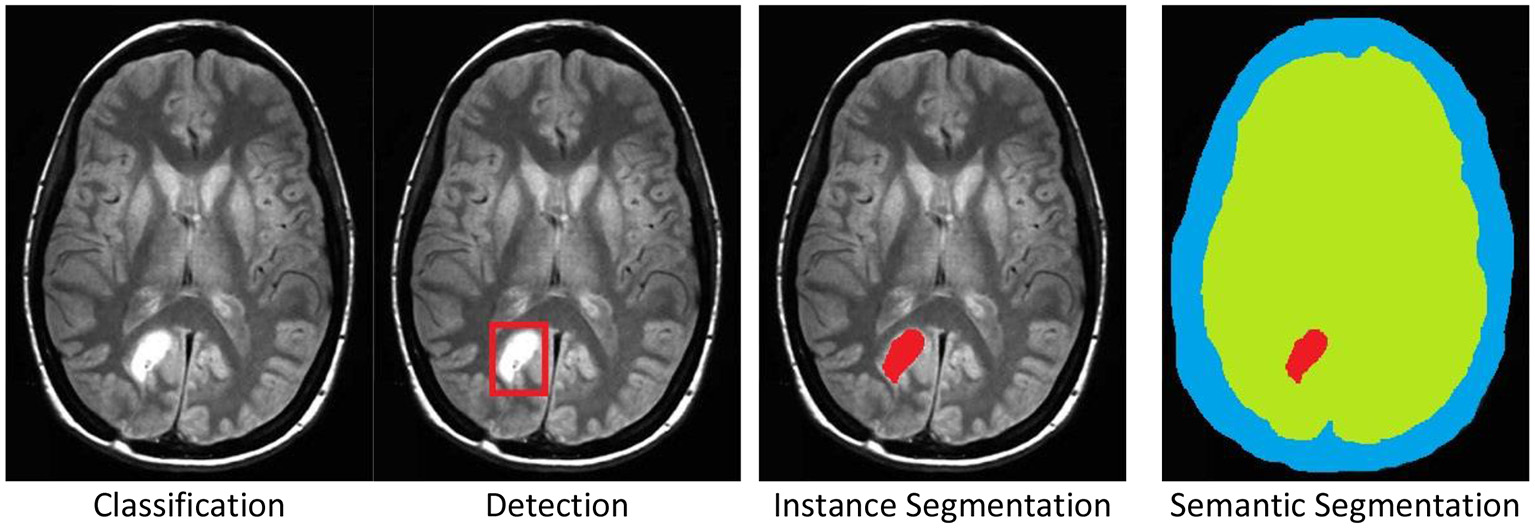

There are four standard labeling cases, (see Figure 1) for examples:

1. Classification: The entire image is associated to a category, e.g., tumor.

2. Detection: A part, or parts, of the image are marked by a rectangle, which is then associated to a category.

3. Instance Segmentation: A part, or parts, of the image are marked by a polygonal boundary, which is then associated to a category. If there are multiple instances of a single category, these instances are marked separately and distinguished.

4. Semantic Segmentation: All parts of the image are marked by polygonal boundaries, which are then associated to a category. If there are multiple instances of a single category, these are not marked separately and not distinguished.

Figure 1. The four standard labeling cases illustrated by a brain tumor example in an MRI scan. Original image was published in Tamije Selvy et al. (7).